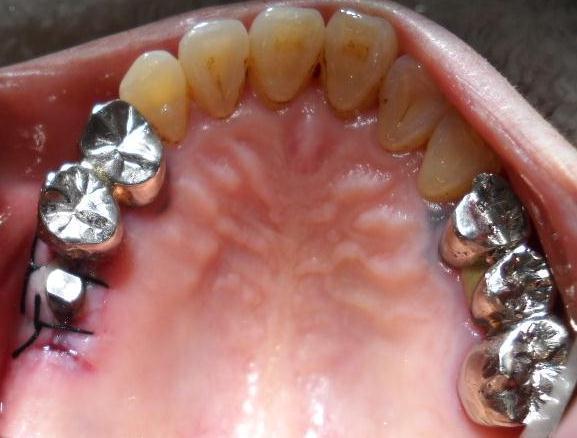

【インプラント処置直後】

【インプラント処置4週後】

手術直後の写真2針縫合

【仮歯装着時】

ひかり歯科のインプラントは1ヶ月でインテ

グレーション骨結合(癒合)することが多い。

【人工歯装着・治療終了】

インプラント噛み合わせ

インプラント側面

(左端の白い歯が

インプラント)